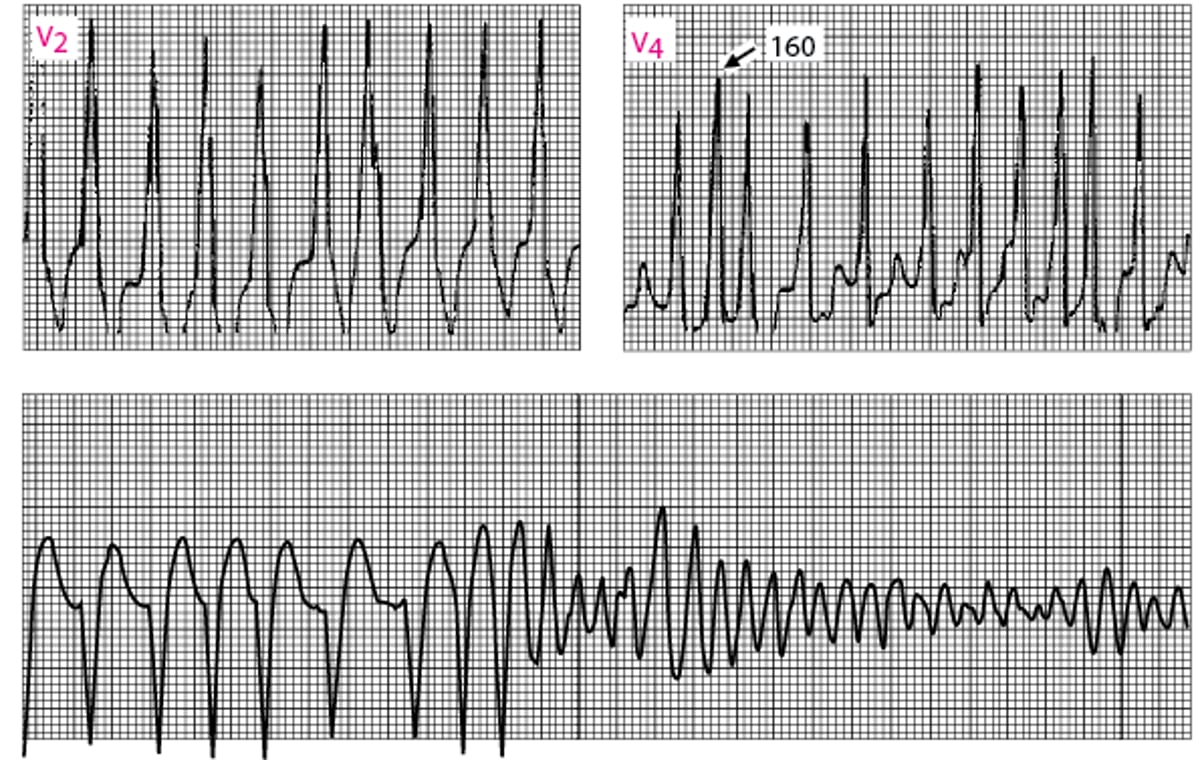

Atrial Fibrillation in Wolff-Parkinson-White Syndrome

Ventricular response is very fast (RR intervals minimum of 160 msec). Shortly thereafter, ventricular fibrillation develops (lead II continuous rhythm strip at bottom).